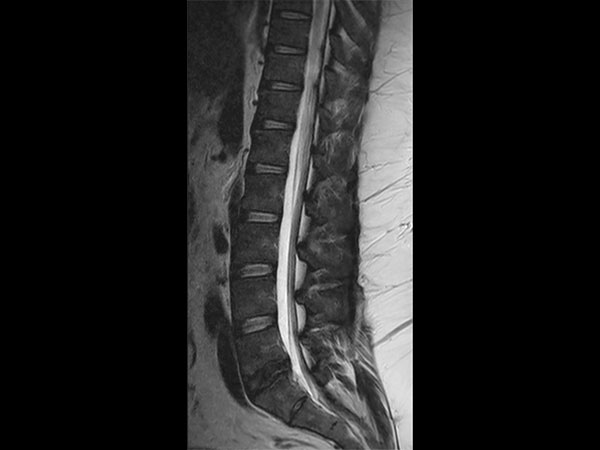

32- year old male patient, 180 kg, with back pain. Was first examined on CT but quality was not sufficient for diagnosis. MRI gave excellent images. Diagnosis: small protrusion of the disc L5/S1, no meningioma.